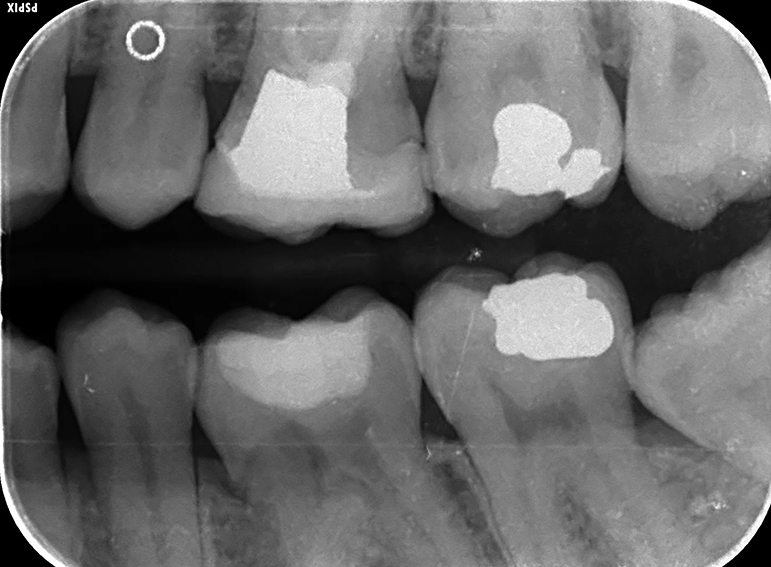

Implant to replace a molar with external cervical resorption.